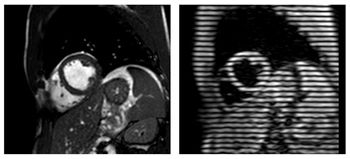

CHICAGO - Magnetic resonance images can detect significant strain on the heart following consumption of energy drinks high in caffeine and taurine.